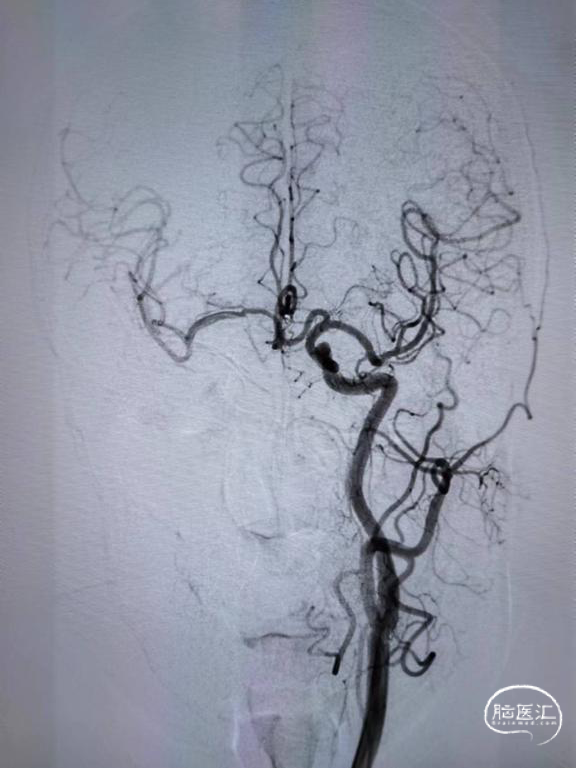

DSA示:右侧颈内动脉起始段闭塞,颈外动脉通过眼动脉代偿至眼动脉,前交通级后交通均开放,代偿右侧大脑中动脉供血。